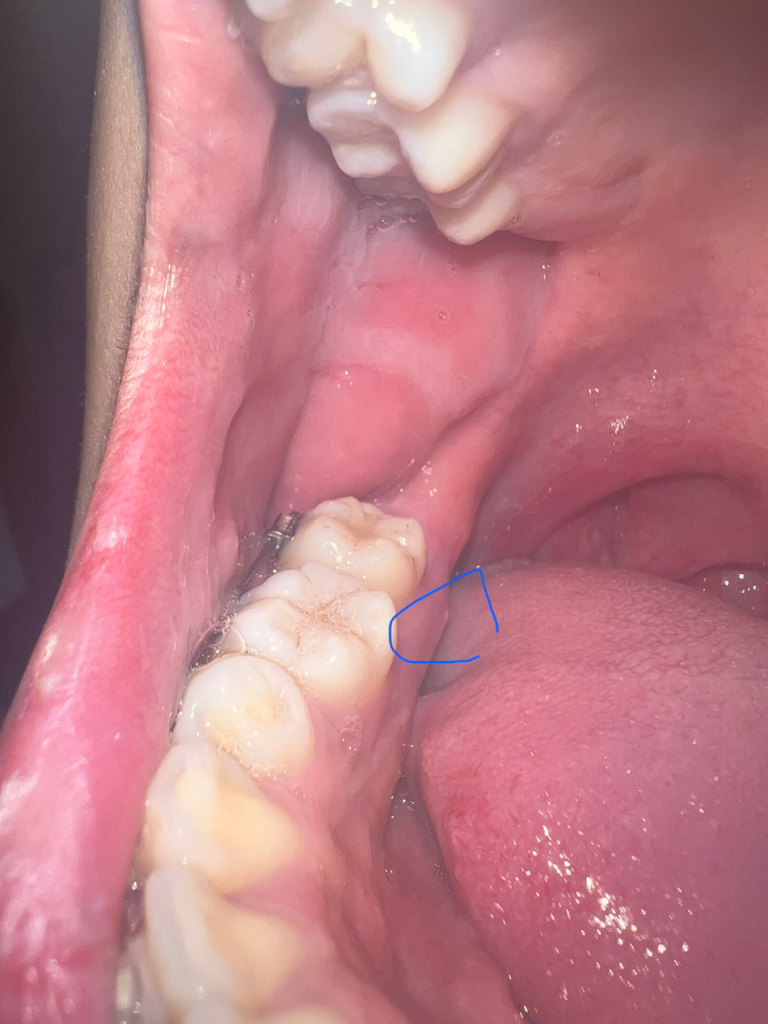

뼈가 튀어 나와서 자극을 받아서 그러는거 같습니다. 계속해서 불편하시면 마취하고 튀어나온 부분을 다듬으시면될것같습니다.

뼈가 튀어나와서 입안으로 돌출되다보니 구내염처럼 큰 불편감을 주는 경우인것 같습니다.

만약 계속 상처가 아물지 않는다면, 치과에서 뼈가 튀어나온부위만 살짝 다듬으면 한결 빠르게 치유될 수 있는데, 해당부(혀쪽)으로는 중요한 해부학적 구조물(설신경,혈관 등)이 지나가기 때문에 치과에서 치과의사의 정확한 진단후 치료가 가능합니다.

일단 우툴두툴한 표면은 뼈의 형태로 인한 것이 맞는 것 같습니다

그리고 잇몸 염증이 생긴 상태같은데 교정 중인 경우 교정력에 의해 잇몸 염증이 생기는 경우가 종종 있습니다.

일반적인 골융기는 특별히 자극이 가해지지 않는이상 통증이 있을 일이 없고 잇몸 염증에 의해서는 통증이 있을 수 있습니다